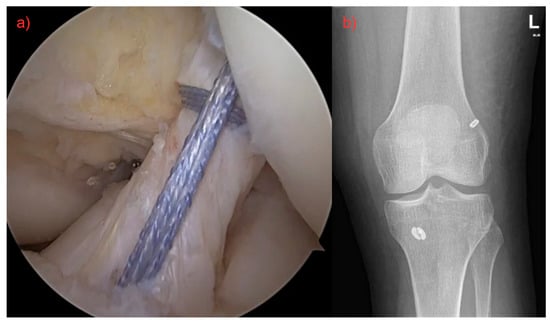

The patient was placed in supine position for both surgical techniques included in this study—primary repair and ACL graft reconstruction. Standard leg preparation and cover-up were carried out. Arthroscopic diagnosis through standard anterolateral and anteromedial portals was performed. Associated injuries (e.g., meniscal tears, osteochondral defects, etc.) were treated first, followed by ACL surgery, and everything was performed at one time. ACL reconstructions were performed using hamstring autografts. The all-inside technique was used in all cases, with an average length of surgery of 62 ± 4 min. The primary repair technique with InternalBrace augmentation was exclusively used for all patients in group 2. The distal LCA stump is stretched using a grasper to assess its length and decide whether it is suitable for primary repair of the ligament. A tibial guide is inserted through the AM port and placed centrally at the distal LCA insertion site. A 2.4 mm diameter wire is inserted through the guide, and if the position is satisfactory, the tibial canal is drilled along the wire with a 4.5 mm diameter cannulated drill. Using a wire with a loop, an auxiliary fiber is passed through the tibial canal and the base of the LCA, which is temporarily brought out of the joint through the AM port. Then, the distal LCA stump is sutured using FibreLink (Arthrex, Naples, FL, USA). The femoral canal is drilled in flexion of the knee joint with a 4 mm diameter wire. FiberLink with a stitched ligament and the TightRope implant with FiberTape (both Arthrex, Naples, FL, USA) is then pulled through the outer cortex. By tightening the individual ends of the fibers proximally alternately, the staple is fixed from the TightRope implant to the lateral cortex of the femur. Then, the FiberLink is knotted with a stitched ligament in extension to the femoral part of the TightRope implant. The suture is tightened and the ACL is toned so that full range of motion in the joint is maintained while achieving anteroposterior stability (Figure 1). The average length of surgery was 43 ± 3 min.

Figure 1. (a) Surgery of ruptured ligament by using FiberLink (Arthrex©), both fibers were pulled through the femoral canal, tightened, and fixed with an anchor. Final result with definitive ACL restoration. (b) Postoperative X-ray.